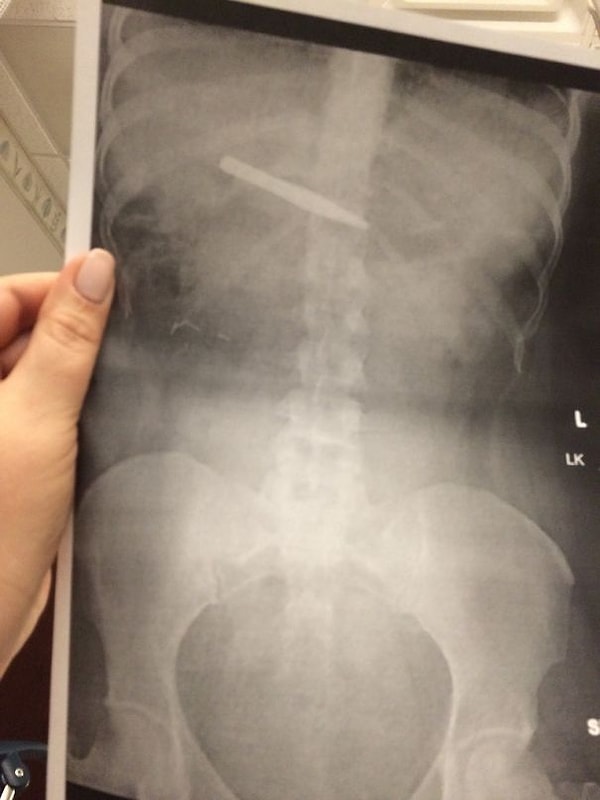

16. «Моя ненаглядная проглотила щипчики для бровей»